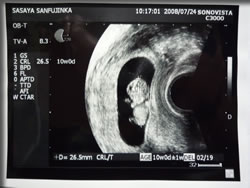

8月9日:48mm

ついに超音波検査の写真をもらったのら。

しかも、超音波検査しているときのビデオまでもらったのら。

8月8日時点でのベビちゃんの大きさが 48mm。

それでも 心臓が動いてて、

もぞもぞ 動いてて、

手も足もはえてて、

すごい。